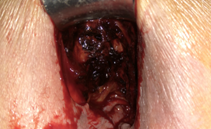

Μπλε βέλος — Άνω χείλος πρωκτοτομής. Κίτρινο βέλος — Νεόπλασμα ορθού (Ευγενική παραχώρηση Dr. V. Penopoulos)